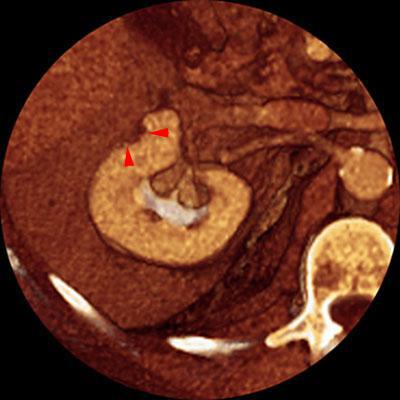

Recidiva local de hipernefroma